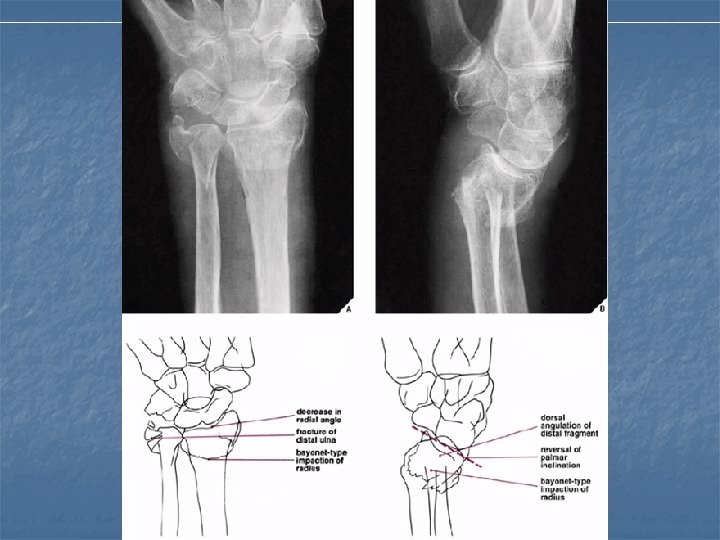

Colles Fracture n n n Most frequently encountered injury to the distal forearm. Fall on the outstretched hand with forearm pronated in dorsiflexion. Age usually above 50 y; F>M. Extraarticular 2 -3 cm away from articular surface of radius. Associated # of ulnar styloid process